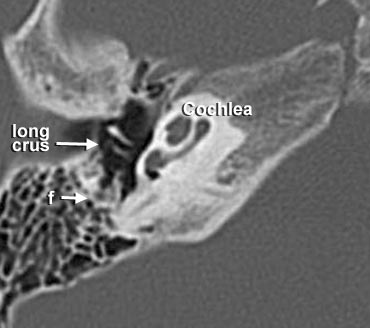

- A = Hang chũm (Antrum)

- f = Dây thần kinh mặt

- long crus = Ngành dài của xương đe

Trong hình ảnh này ở mức ống tai trong, đoạn nhĩ của dây thần kinh mặt được thấy nằm ngay phía trong và song song với thành của thượng nhĩ.

Ở mức này, ống thông hang (aditus ad antrum) được thấy rõ. Đây là đường thông nối giữa hòm nhĩ và hang chũm.